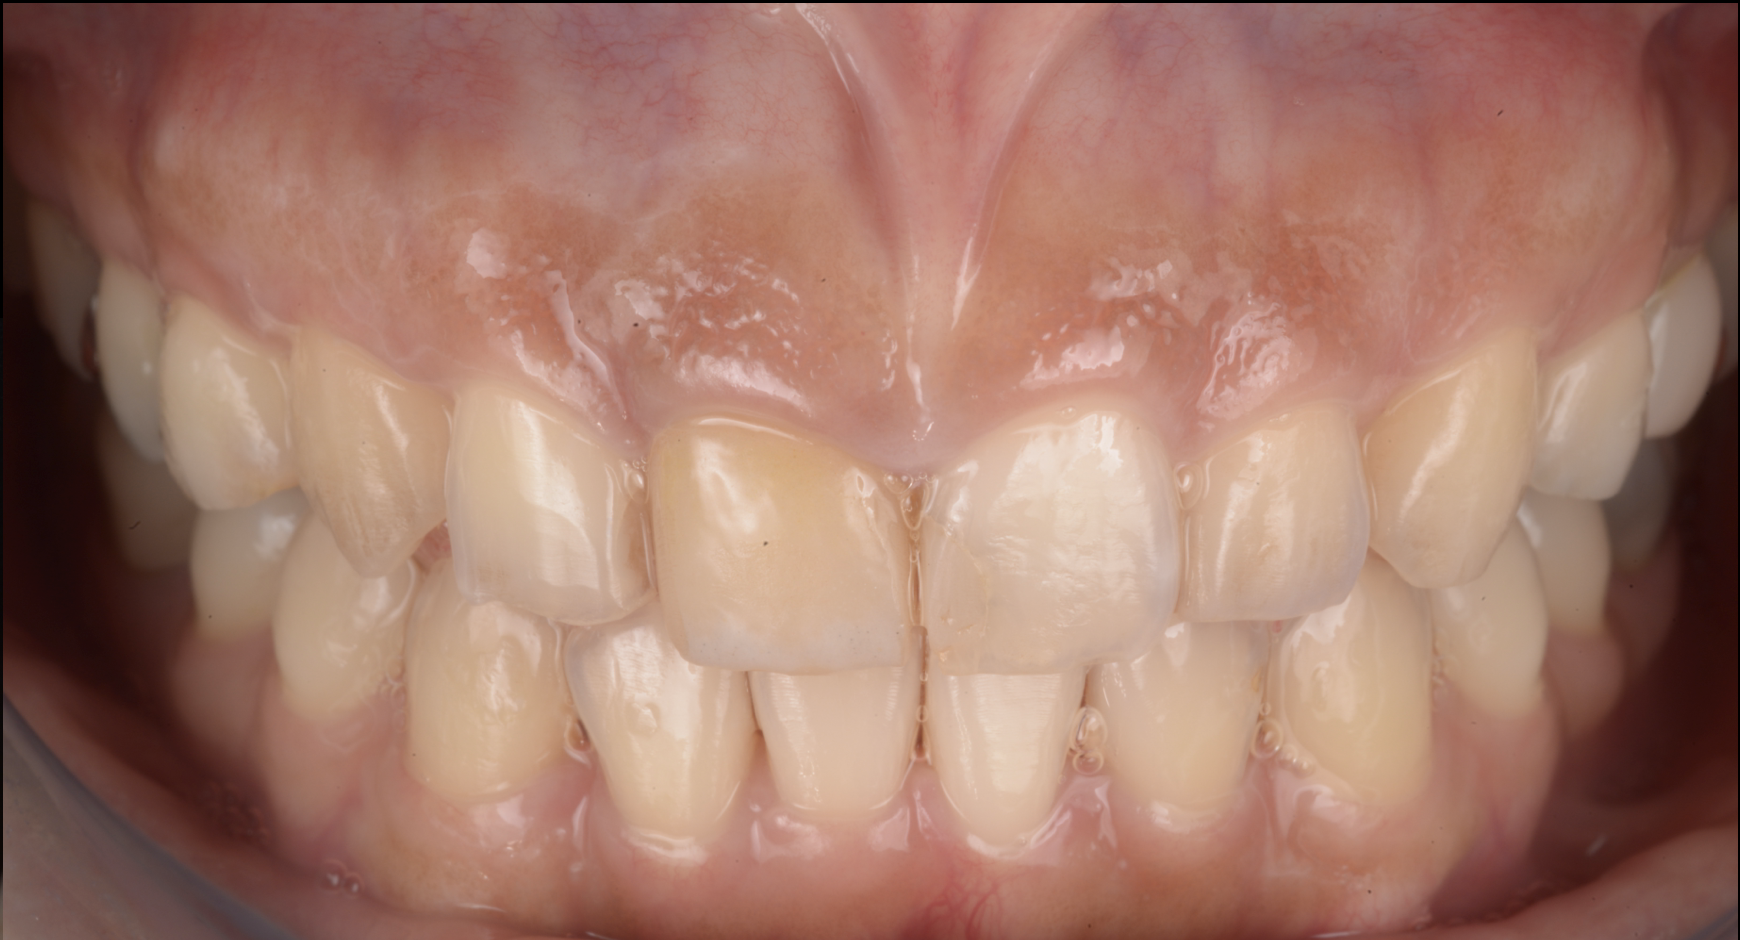

治療前

治療後